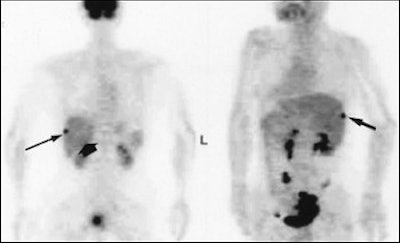

A 62-year-old woman with heterogeneous cyst of the liver. Abdominal CT scan (above) shows heterogeneous cystic lesion with suspected parenchymal liver metastasis (arrow), but not peritoneal implants on liver surface. Whole-body FDG-PET (below) scan in maximum intensity projection does not indicate significant FDG uptake in liver parenchyma (thin arrows) beside hot spot at liver surface (thick arrow). Yoshida Y, Kurokawa T, Kawahara K, Tsuchida T, Okazawa H, Fujibasyashi Y, Yonekura Y, Kotsuji F, "Incremental Benefits of FDG Positron Emission Tomography over CT Alone for the Preoperative Staging of Ovarian Cancer," (AJR, January 2004, Vol.182, pp. 227-233).